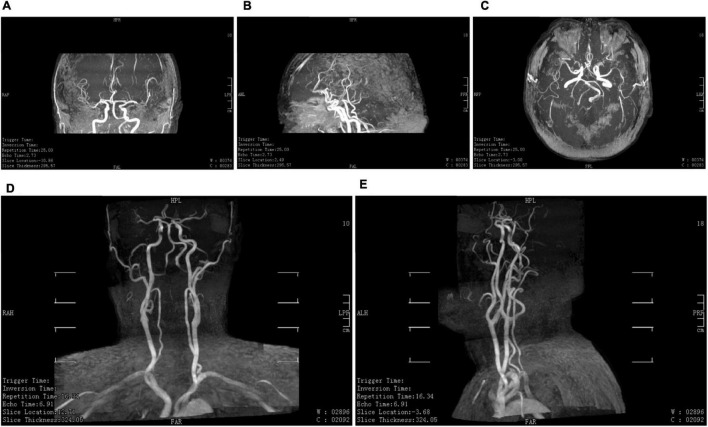

这项研究共有20名参与者,其中5名男性和15名女性,他们都有能力并熟悉独立倒立。除一名参与者外,所有参与者都有至少一年的瑜伽经验。年龄在10-59岁之间;中位年龄为43岁。在研究参与者中,17人在海拔2000米的地方进行了评估,其余人在海平面进行了评估。瑜伽倒立(sirsasana) 研究人员通过对颈~内动~脉的超~声检查来测~量~血~流。当参与者仰卧,然后倒立,然后再次仰卧时,测量...

今天和大家分享一篇关于瑜伽倒立练习的文章。关于各种瑜伽练习在生理上的影响,有很多观点围绕着这些练习。瑜伽倒立练习 其中一些源于对描述实践的经典梵文文献的解释。其他信息多来自于近年的一些研究来源产生的,在瑜伽界...在这项研究中,作者验证了 大脑血流量的自动调节,即身体将大脑血流量保持在一定健康值内的方法,在我们倒立时,只要我们在其他方面健康,大脑血流量

许多瑜伽习练者认为,头倒立(sirshasana)会增加大脑血流量,但这与脑血流量自动调节稳定的机制并不相符,俄罗斯圣彼得堡国立大学的研究团队希望通过对流经颈内动脉(Internal Carotid Artery,ICA)进入大脑的血流量进行检测,探讨头倒立对脑血流量的影响。研究样本 样本数量为20(5男15女),年龄在10岁到50岁之间(年龄中位...

研究结果明确显示:与我们常听到的解释相异,头倒立并不会增加大脑血液供应;相反,倒立期间,流经颈内动脉血流量会在脑血流自动调节机制下,出现一定程度的下降。另外,在 ...

1. 一项针对20名有经验的瑜伽练习者的研究发现,在头倒立期间,其中17名健康参与者的颈内动脉血流量并未增加,反而略有下降。研究者认为这是脑血流自动调节机制正常工作的结果。

1. 原文摘录:研究结果明确显示:与我们常听到的解释相异,头倒立并不会增加大脑血液供应;相反,倒立期间,流经颈内动脉血流量会在脑血流自动调节机制下,出现一定程度的下降。……20位受试者中的17位,在倒立期间并没有出现颈内动脉血流量增加的情况,流经左颈内动脉的血流量先是在倒立时减少,而在体式效应过后,血流量又恢复到基本水平。

链接:https://m.toutiao.com/article/6850646721198817805/

信源名称:今日头条(编译自《替代和补充医学杂志》2019年研究)

信源发布时间:2020-07-18

Conclusions: Contrary to popular belief, Sirshasana does not increase blood flow to the brain through the ICA, but results in predictable reduction in cerebral ...

2. 美国国立卫生研究院(NIH)收录的一项于2019年发表在《替代与补充医学杂志》的研究,通过超声波测量了20名倒立练习者颈内动脉的血流。结果显示,绝大多数健康受试者在头倒立时,流向大脑的血流量并未增加,反而出现了符合自动调节机制的“可预见的减少”。

1. 原文摘录:Contrary to popular belief, Sirshasana does not increase blood flow to the brain through the ICA, but results in predictable reduction in cerebral blood delivery in compliance with known mechanisms of autoregulation of cerebral blood flow.

链接:https://pubmed.ncbi.nlm.nih.gov/31219304/

信源名称:美国国立卫生研究院 PubMed (Headstand (Sirshasana) Does Not Increase the Blood Flow to the Brain)

信源发布时间:2019-08-01

2. 原文摘录:研究结果明确显示:与我们常听到的解释相异,头倒立并不会增加大脑血液供应;相反,倒立期间,流经颈内动脉血流量会在脑血流自动调节机制下,出现一定程度的下降。